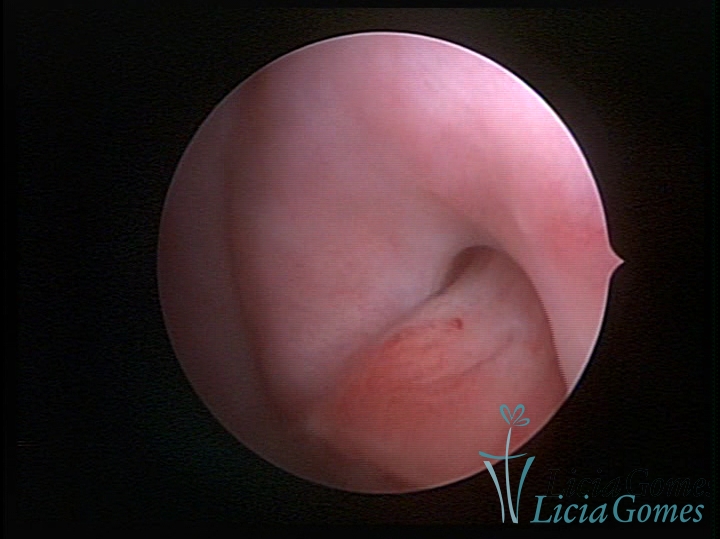

ENDOCERVICAL POLYPS

Benign tumors resulting from the reactive focal proliferation to inflammatory processes or hyperestrogenism situations, which may be sessile (with a large implantation) or stalked.